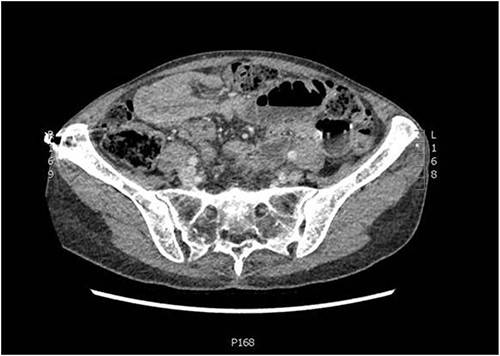

Following the investigations, she was diagnosed with intussusception causing small bowel obstruction in a virgin abdomen and was admitted to the general surgical unit for further management. Initial management included insertion of a nasogastric tube, fluid resuscitation and she was kept nil by mouth. She underwent operative management of the small bowel obstruction caused by intussusception under general anaesthesia. The operative findings included some serous peritoneal fluid and mid small bowel intussusception causing small bowel obstruction (Fig. 3). There was a palpable hard lump at the lead point of the intussusception, and there was no other palpable lumps in the mesentery, small or large bowel. A mini laparotomy was made, and a wedge of small bowel with macroscopically clear margins was resected. The rest of the diagnostic laparoscopy was unremarkable. She had an uneventful postoperative recovery and was discharged day 4 post-operation. Histopathology confirmed a 3.1 cm plasmacytoma deposit in the small bowel.

Intraoperative image demonstrating the small bowel intussusception.